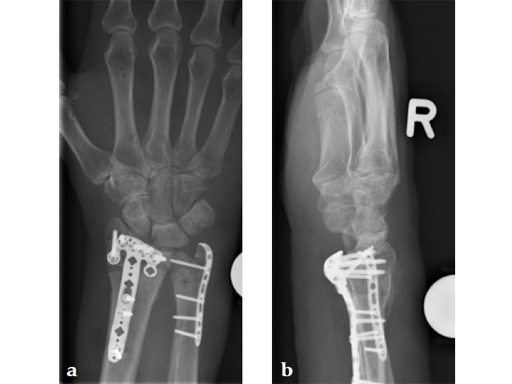

Fig 4ab X-rays 3 days postoperatively: removable splint, early motion with physiotherapy.